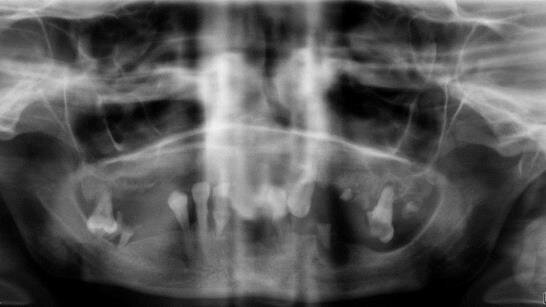

54-letnia pacjentka, ogólnie zdrowa, zgłosiła się do poradni chirurgii stomatologicznej i implantologii celem sanacji jamy ustnej oraz leczenia implantologicznego żuchwy. W badaniu fizykalnym stwierdzono obecność pozostawionych korzeni oraz zębów paradontalnych i zmian zapalnych. (Ryc. 1). Po rozmowie z pacjentką uzgodniono zastosowanie w żuchwie 2 implantów w pozycjach kłów i konstrukcję protezy całkowitej opartej na łącznikach typu „locator”. Ze względów ekonomicznych pacjentka zgodziła się na użytkowanie klasycznej protezy całkowitej osiadającej w szczęce. Przed wykonaniem zabiegu przygotowano protezy całkowite górną i dolną.

Przyjęto 12-tygodniowy protokół gojenia zamkniętego. W tym czasie wykonano 3 wizyty kontrolne w odstępach 4-tygodniowych. Pierwsza wizyta nie wykazała żadnych nieprawidłowości w osteointegracji, pacjentka nie zgłaszała dolegliwości (Ryc. 2). Utrzymanie protezy górnej pacjentka określiła jako wystarczająco komfortowe, ale zgłaszała trudności w użytkowaniu protezy dolnej.

Kolejna kontrola została wykonana po następnych 4 tygodniach. Także i tym razem pacjentka nie zgłaszała bólu, jedynie dyskomfort w utrzymaniu dolnej protezy oraz utrudnione spożywanie posiłków. W badaniu wewnątrzustnym stwierdzono odleżynę po stronie językowej w okolicy 33. Ponadto, podczas palpacji tego fragmentu części zębodołowej, na granicy dziąsła i dna jamy ustnej stwierdzono miejsce poddające się uciskowi, który wywoływał niewielką tkliwość. W rtg pantomograficznym i TK stwierdzono w okolicy wierzchołka implantu 33 obecność ogniska lizy tkanki kostnej z uszkodzeniem blaszki językowej. Zmiany przypominały „zapalenie okołowierzchołkowe”. Ognisko powyższe osiągnęło rozmiar 6 mm w wymiarze przedsionkowo-językowym oraz 7 mm mezjalno-dystalnie. Blaszka kostna przedsionkowa nie została zniszczona, tkanka kostna przedsionkowo miała szerokość 4 mm w rzucie zapalenia. Co ciekawe, kość i tkanka miękka wokół szyjek implantów nie wykazywały żadnych zmian patologicznych (Ryc. 3-6).